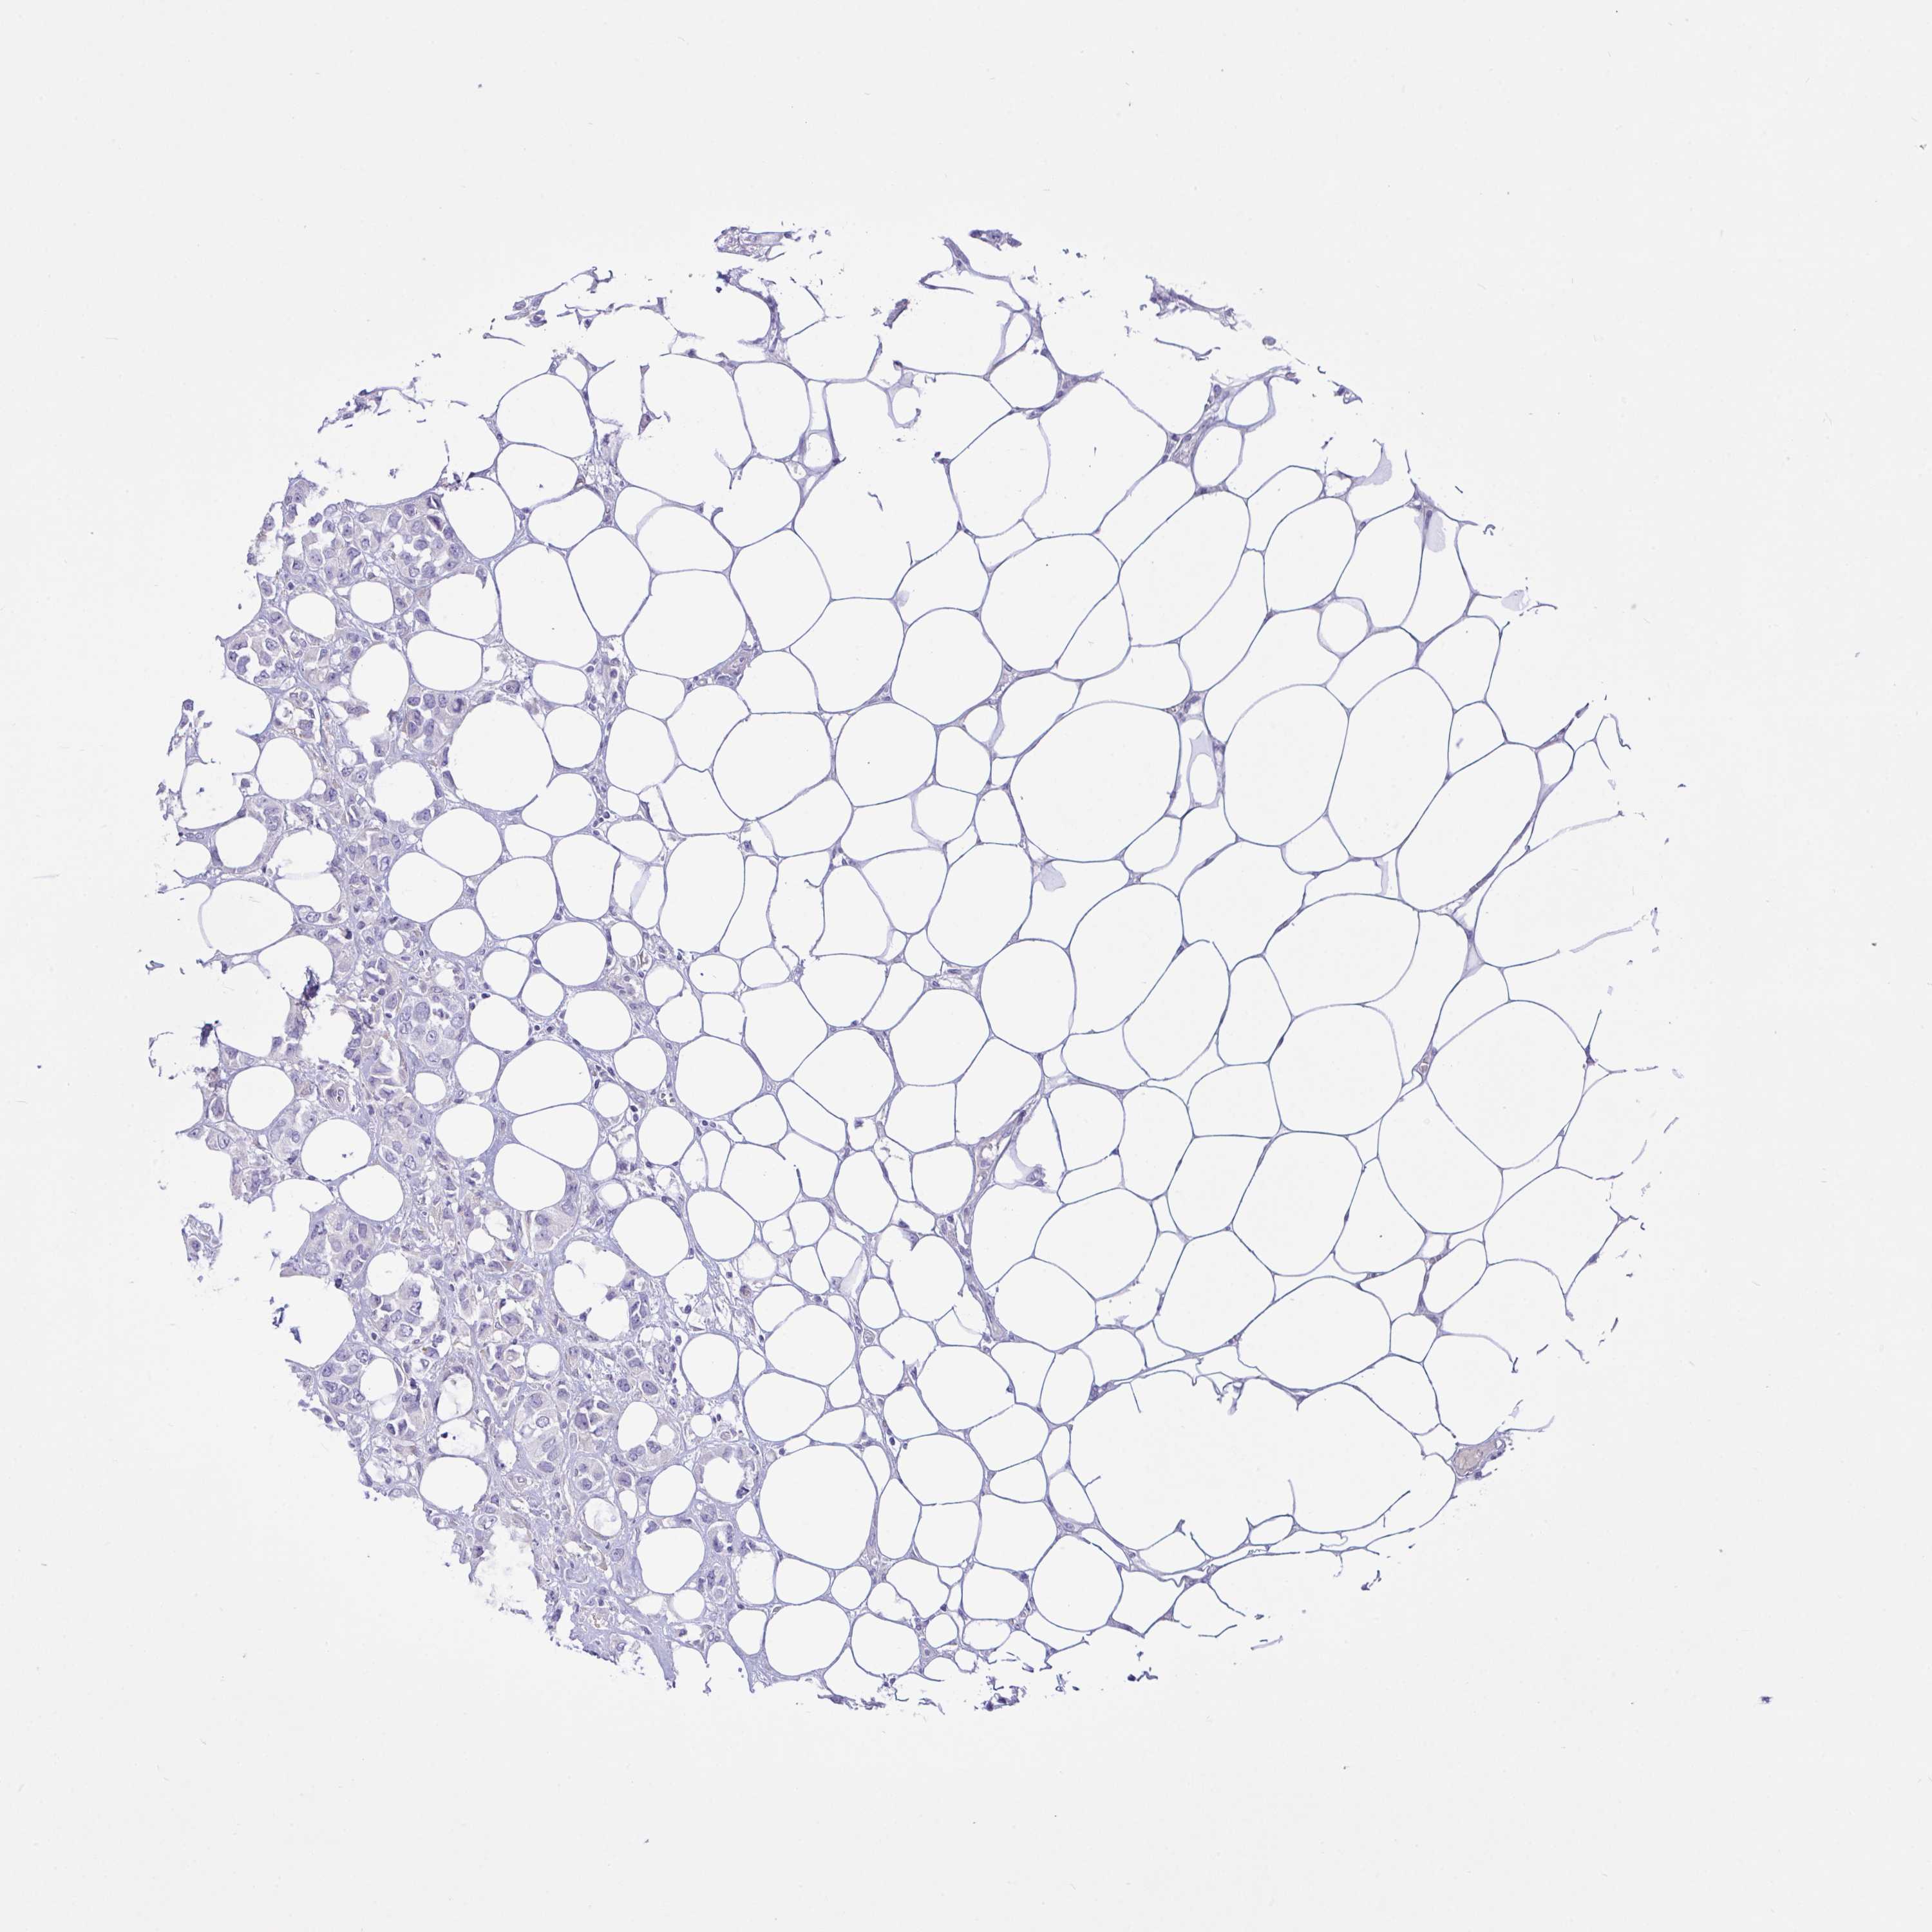

Breast cancer

Human cancer